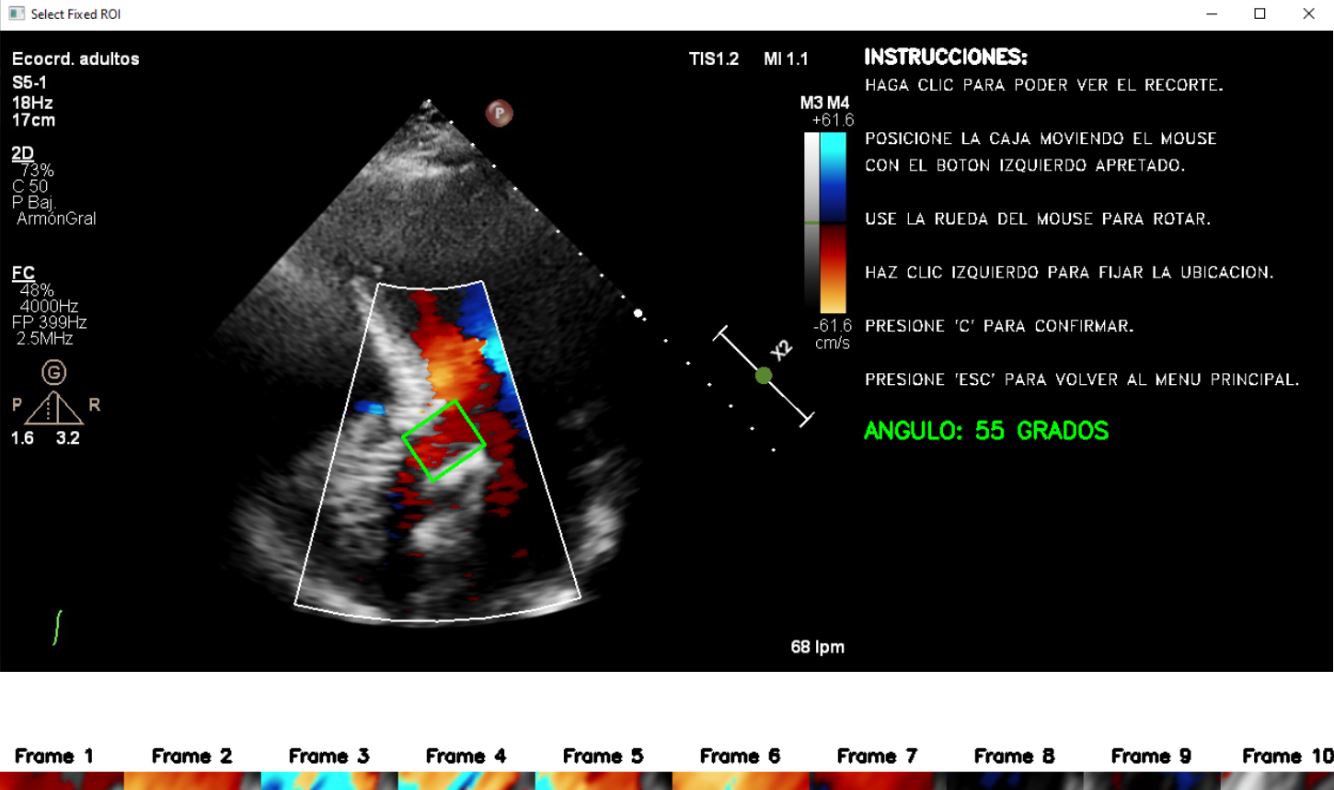

El reemplazo valvular aórtico es una de las intervenciones invasivas cardiovasculares más frecuentes. La disfunción valvular protésica es una de las complicaciones estructurales más prevalentes en el seguimiento de mediano y largo plazo de estas intervenciones. Una de las variables hemodinámicas que se han asociado con la presencia de disfunción valvular es la turbulencia del flujo sanguíneo. En este plan de trabajo proponemos evaluar la presencia de turbulencia del flujo sanguíneo en el seguimiento clínico y ecocardiográfico de pacientes con reemplazo valvular aórtico y analizar la potencial asociación entre este fenómeno y el desarrollo de disfunción valvular protésica. Nuestra hipótesis de trabajo es que la turbulencia del flujo sanguíneo contiene información valiosa acerca de las condiciones hemodinámicas a nivel de la válvula protésica que se asocian al desarrollo de disfunción valvular protésica.

Palabras clave: Válvulas cardíacas, Estenosis aórtica, Reemplazo valvular, Turbulencia, Eco Doppler.

Equipo: Azul Giraud, Tomás Mendivil, Teresa Politi, Daniela S. Andres

En asociación con: Instituto Cardiovascular Buenos Aires, Hospital Británico, Institut Jean Le Rond D’Alembert - Sorbonne Universités.